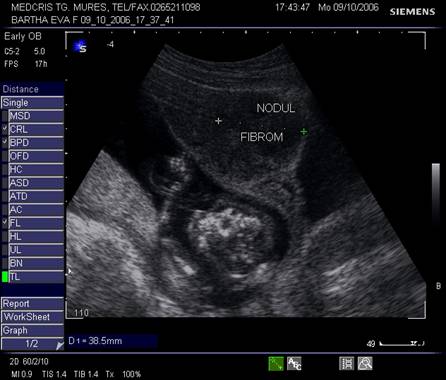

9.Sarcina si fibromul uterin

Cea mai comuna tumora uterina - leiomiomul - poate fi detectata si masurata inca de la inceputul sarcinii. Fibromul poate complica sarcina in functie de marime si pozitie. Nodulul subseros pediculat foarte rar se poate complica, in schimb nodulul submucos sau intramural creste riscul de avort spontan sau nastere prematura, dar peste 75% din aceste paciente duc sarcina la termen. Cea mai frecventa complicatie a fibromului in sarcina este necroza aseptica (25%) de obicei moderata, ea poate aparea si in lauzie. Cresterea fibromului in sarcina a fost notata in circa 22% dintre fibroame.[12]

Fibromul apare de obicei hipoecogen in uterul gravid, trebuind masurat si observat pe parcursul sarcinii.

Ocazional o contractie uterina mimeaza un fibrom submucos, imagine care nu poate fi reprodusa ulterior.

Fig nr. 91. Nodul fibromatos submucos si sarcina

Fig. nr. 92. Nodul fibromatos intramural hipoecogen,

alaturi de sarcina de 12 saptamani